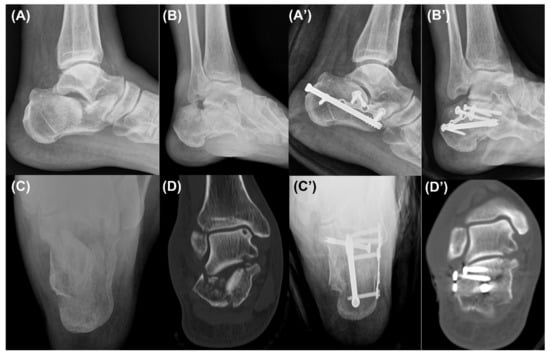

Surgical Treatment Using Sinus Tarsi Approach with Anterolateral Fragment Open-Door Technique in Sanders Type 3 and 4 Displaced Intraarticular Calcaneal Fracture

2.2. Surgical Technique